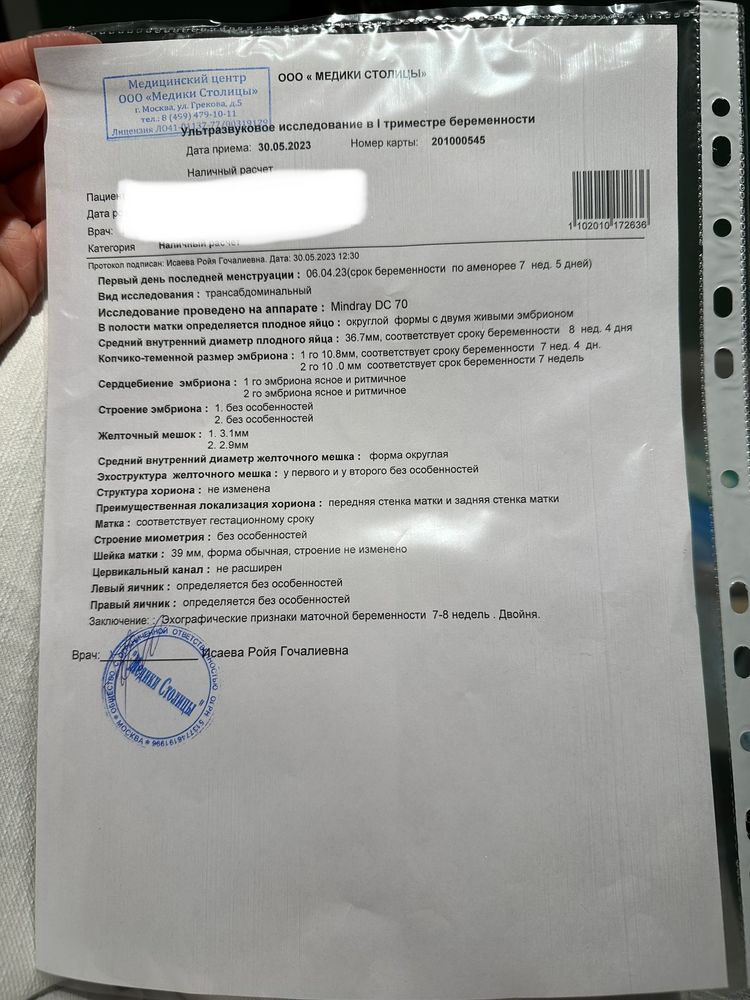

Девушки, очень нужна помощь! Сделали узи, сказали что у меня двойня ( я в шоке, первая беременность). Хочу понять какая это именно двойня, два мешочка желточных, хорионы по передней и задней стенке. Что это значит?

Перегородку, пока, не видно, поэтому монохориальная моноамниотическая двойня. Чуть позже могут увидеть перегородку и будет монохориальная диамниотическая

Таро Расклады, у вас получается 1 вариант, раз хорионы по разным местам

Таро Расклады, нет первый вариант это Ди-Ди с этой двойней два плодных яйца и каждый в своем домике,а у автора одно пя на двоих это моно-ди

Таро Расклады, и что ?:) прикрепились и прикрепились ) пуповинки же разные...

ди ди на Узи сложно спутать ) там прям два отдельных домика, например:

Пока что это монохориальная моноамниотическая, позже могут найти перегородку

Хорион один, плодный пузырь один==> монохориальная точно, но вот диамниотическая или моноамниотическая скажут позже, все зависит от того найдут ли между ними внутри плодного пузыря перегородку, чаще их находят, ну это и лучший вариант чем моно моно. Вообще, такие двойни спокойно могут быть ди ди, ди ди это не только когда два разных плодных яйца, это когда у каждого свой амнион и своя плацента именно тогда двойня будет ди ди.

Монохориальная диамниотическая,одно плодное яйцо это Моно,а остальное по два,это Ди

МоноДи скорее всего. Близнецы, а не двойняшки. Будут одного пола. Поздравляю Вас🌷🌷🌷. Чихните заразным чихом😉